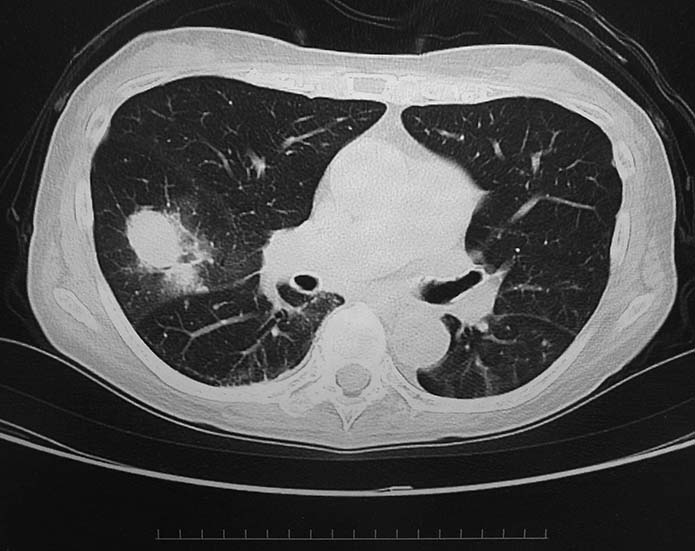

• X線検査では,通常,両肺の中・下部領域に多数の空洞化した転移性結節が認められる. 肺外への浸潤は極めて稀. 皮膚,中枢神経系,肝臓,腎臓などにも転移が見られる.

5年前から胸部CTで両肺底部にすりガラス影が出現, 間質性肺炎を指摘された. 2年前に治療強化のためエタネルセプト(TNF-α阻害薬. 商品名エンブレル)が導入された(T-spot test陰性確認後).

今月定期受診で1年ぶりにchest X-pを撮影. 両肺野に多発結節影が指摘されて受診となった.

chestX-pとCT.サムネイル画像クリックで大きな画像がみられます.